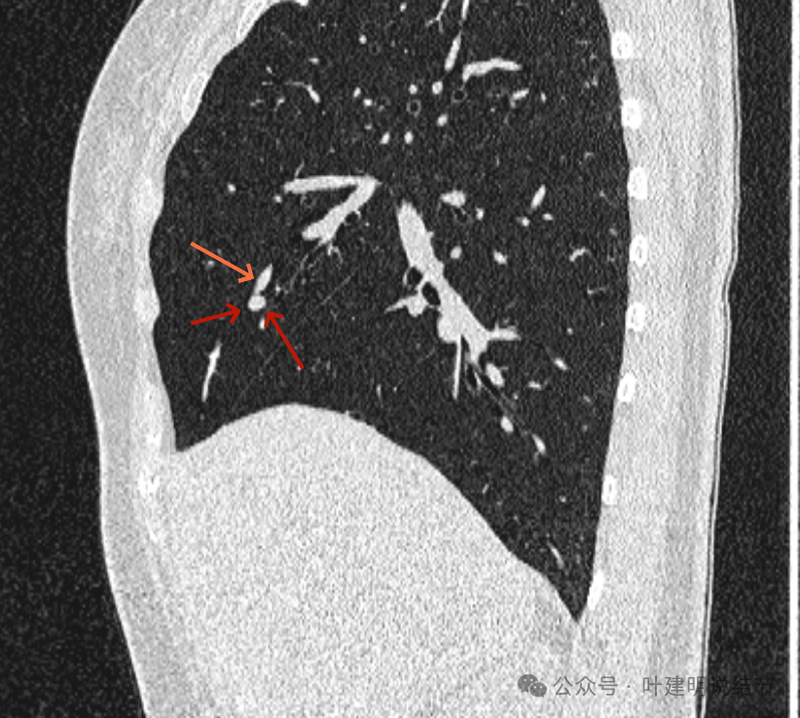

再看矢状位影像:

桔色的是血管,红色的是病灶,两者之间有间隙仍用天蓝色细线标注。

紧挨但仍有缝隙的。

血管贴着病灶,病灶表面略有毛糙之处。

血管有形成轻微血管弯征,两者紧贴。

两支血管夹着病灶,密度不同,有低密度间隙。

病灶与两侧血管关系均密切,明显觉得密度是不一样的,血管的密度略高,结节的略低。

病赤与血管在蓝色箭头处失去间隙,像是侵蚀血管壁,造成血管受侵犯破坏。病灶是软组织密度的,而且整体看有膨胀感。

病灶密度稍不均。表面不光滑。

病灶与边上血管间隙不清。

桔色箭头所示的血管受压稍有移位。

密度不同,关系密切。

边缘区域也是有膨胀感。

血管与病灶脱开后的样子。

边缘区也是基本上实性的。